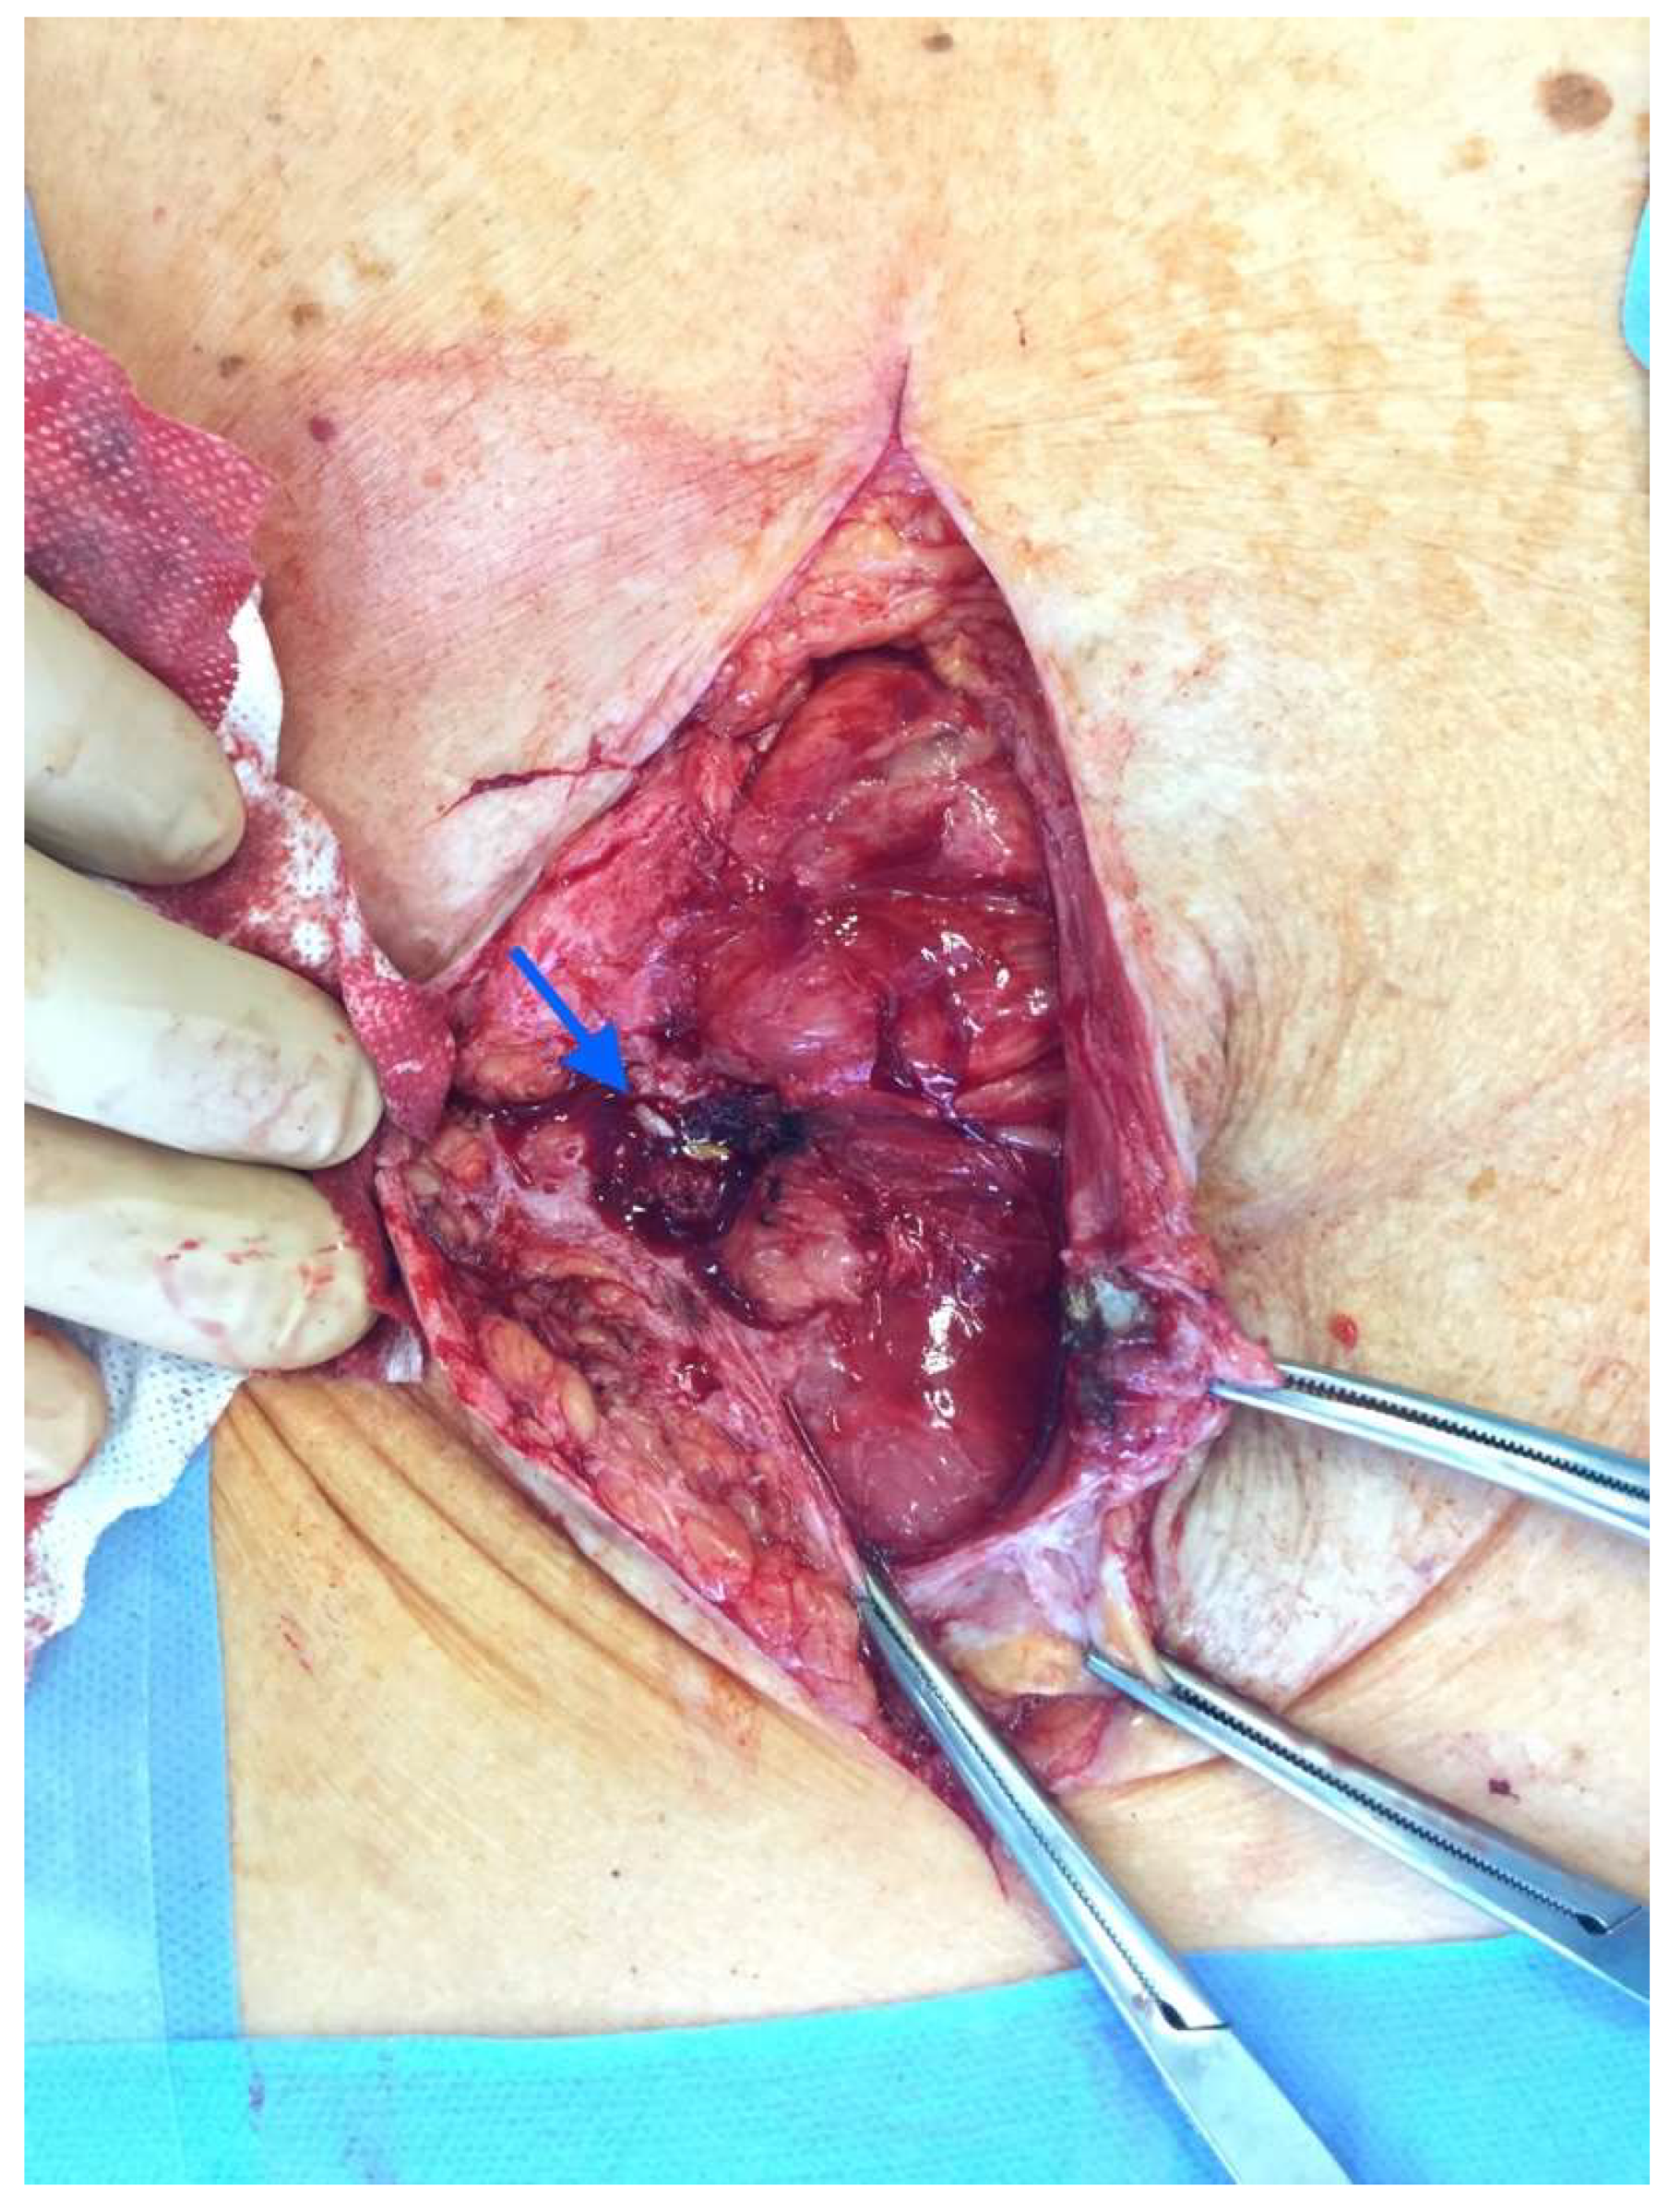

After the optimization of the patient’s nutritional status, a laparotomy, adhaeolysis, and jejunal resection were performed. A conglomerate consisting of the small intestine 80 cm from pl. duodenojejunalis was identified and a metal stent was palpated. The intestines 5 cm proximal to the blockage were found to be hypertrophic and considerably inflated (Figure 2 and Figure 3). The resection of 10 cm of the small bowel with the metal stent was performed and a jejunojejunal anastomosis was formed using a running 3-0 PDS suture (Figure 4).

Figure 3. Enterocutaneous fistula seen in the mobilized small bowel (blue arrow).